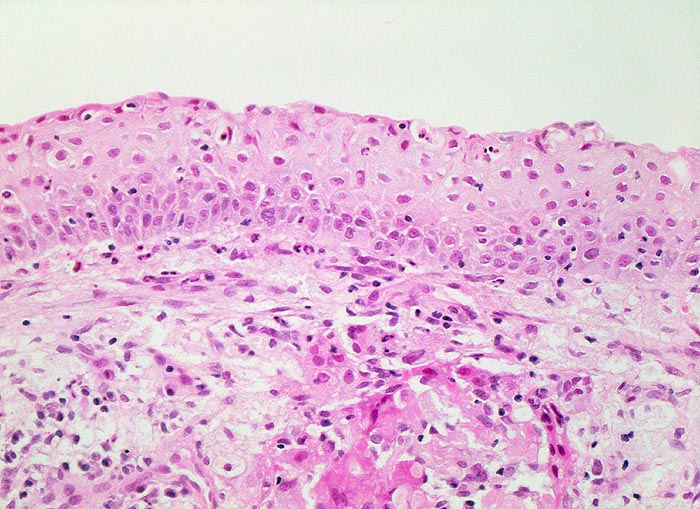

PathoPic – image database / PathoPic ID 4711 - Plattenepithelmetaplasie der Bronchialschleimhaut

Plattenepithelmetaplasie der Bronchialschleimhaut

Nicht verhornende plattenepithelial differenzierte Schleimhaut. Zytoplasmareiche Epithelzellen ohne Atypien mit scharfen Zellgrenzen. An der Oberfläche fehlen Flimmerhaare. Basalzellschicht mit etwas weniger Zytoplasma. Lockeres granulozytäres Entzündungsinfiltrat im Epithel und im subepithelialen Stroma.

Die Plattenepithelmetaplasie ist Ausdruck einer Anpasssung auf chronische mechanische (z.B. Reibe- und Druckpunkte von Trachealkanülen) bzw. chemische (Zigarettenrauch) Irritation. Häufig findet sich eine Plattenepithelmetaplasien ev. mit Dysplasie in der Umgebung eines invasiven Karzinoms.